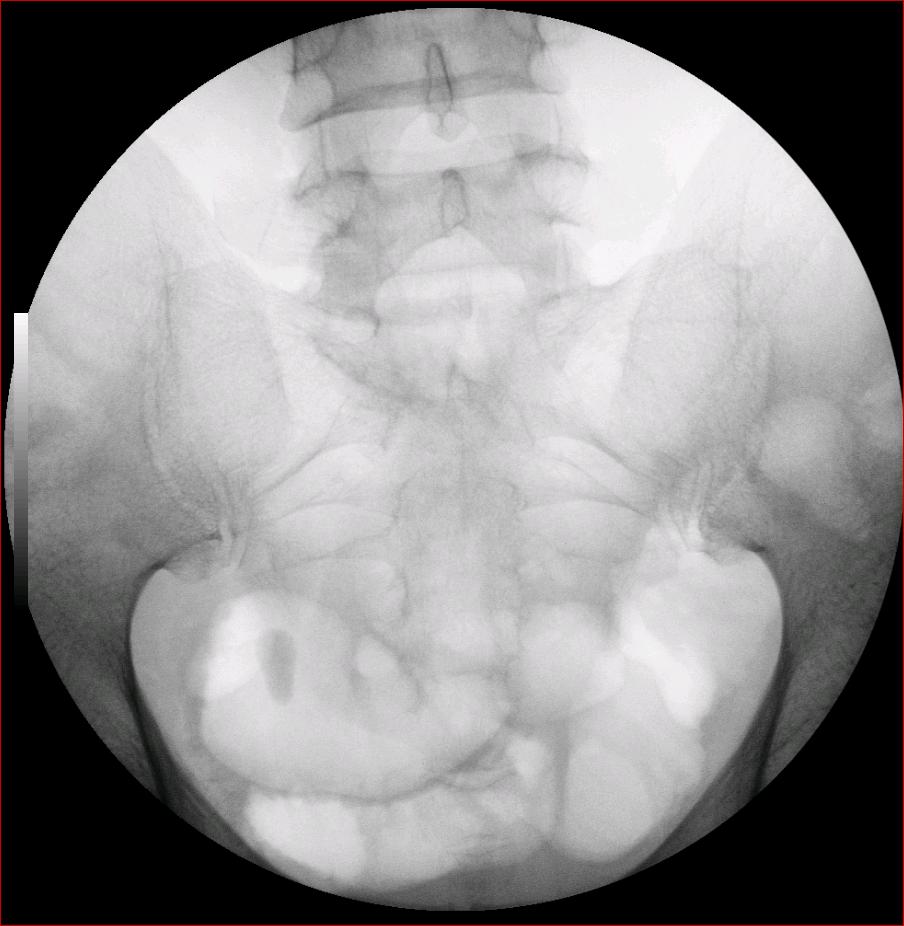

以下是引用luoxinjun在2008-2-18 15:54:00的发言:[br]右肾积水,右输尿管下端结石

以下是引用zhangxiangjun在2008-2-18 21:01:00的发言:[br]右输尿管盆段末端结石,继发其近端输尿管、右肾积水。

以下是引用hexue在2008-2-18 17:33:00的发言:[br]右输尿管下段结石并右肾及右输尿管积水扩张

以下是引用杀毒软件在2008-2-18 16:24:00的发言:[br]右输尿管下段结石,肾盂积水。